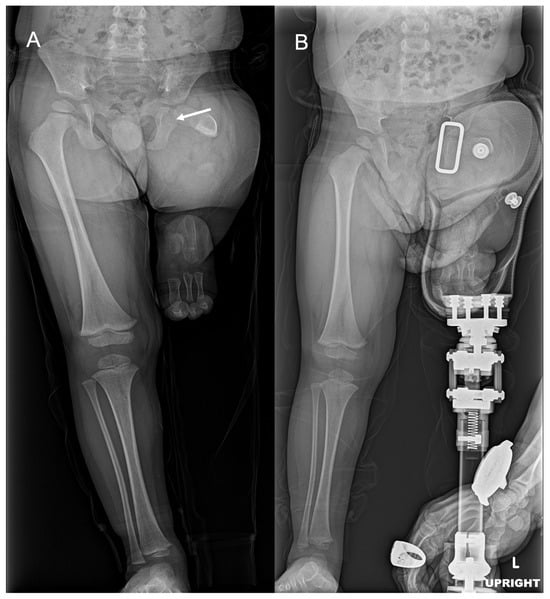

2.2. Case 2

2.3. Case 3